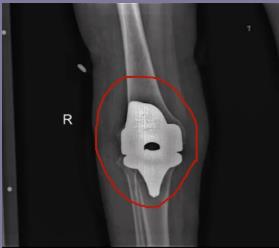

近日淄博市第四人民医院骨二组成功为一例类风湿性关节炎患者成功实施关节置换术。患者因类风湿性关节炎,多年来膝关节不能伸直,关节反复肿胀,行走受限,疼痛无时无刻不在折磨着他,不仅无法工作并且严重影响生活质量。患者入院后,骨科手术团队仔细为患者行体格检查,制定详细的手术方案,术后在骨二组医护人员的精心治疗和护理下,术后五周,患者的双膝基本活动自如。

膝关节置换手术对晚期大关节畸形和功能障碍的患者行关节置换手术治疗是最终有效恢复正常生活及提高生活质量的有效治疗手段。